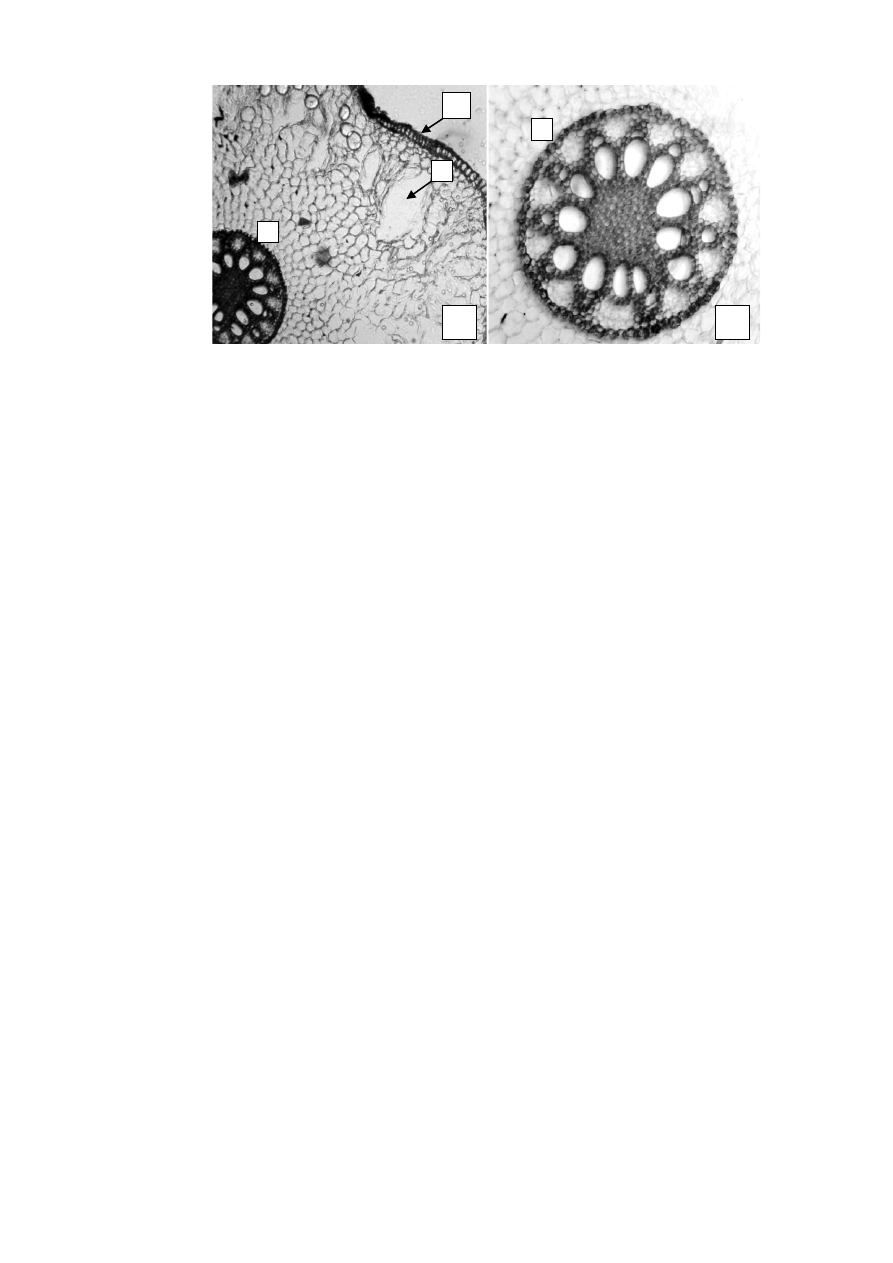

Рисунок 1

–

Чемерицы Лобеля корневища с корнями

:

фрагменты поперечных срезов корневища: 1

, 5, 7 – (56×);  2 – (280×);  3,

6 – (600×); 4 - (900×)

; фрагменты поперечных срезов корней: 7

- (56×), 8 -

(135×): 1 (

а

) –

гиподерма; 2 (б)

каменистые клетки; 3 (в

клетки паренхи-

мы с крахмальными зернами;

4 (

г

), 6  –

рафиды оксалата кальция,

5 (

д

эн-

додерма

; 5,6 (

е

) -

проводящие пучки центрофлоэмные,

7 (

ж

эпидермис,

(

з

межклеточные пространства (аэренхима)

в коре,

7,8 (

и

центральный

осевой цилиндр